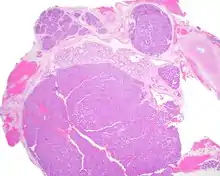

Canalicular adenoma is a type of growth that occurs in human salivary glands. It is a benign growth which occurs in the epithelial cells, and is typically arranged in columns of cells that form interconnecting cords. Canalicular adenoma is a very rare benign neoplasm; it constitutes about 1% of all salivary gland tumors and about 4% of all benign salivary gland tumors.[1][2]

Canalicular adenoma is most common in patients age 70 to 80, with females affected about four times as often as males. Most growths present in the upper lip; some also occur in the a few present in palate or buccal (cheek) tissue as a slowly enlarging mass.[3] The growths will often arise in multiple places at the same time or develop multiple nodes, despite not being clinically invasive or malignant.[1][4]

Canalicular adenoma growths are usually small at the time they are noticed, with an average size of about 1.6 cm.[1] Their histologic appearance is very distinct, with a channel-like pattern between cords and ribbons; the pattern has been described as resembling a "string of pearls."